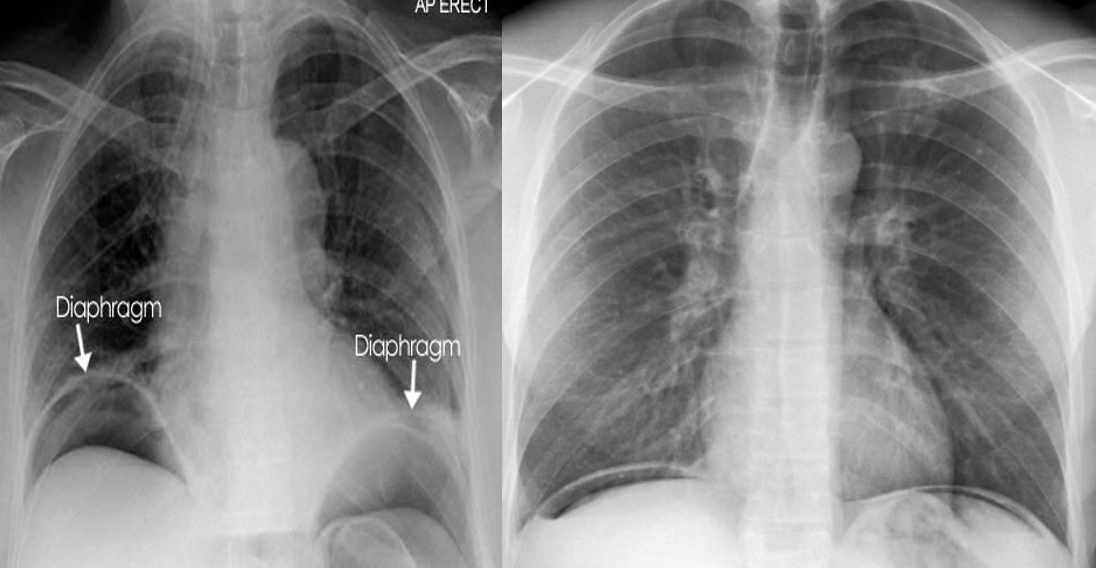

abdominal conditions present as chest disorder

- Air under the domes of diaphragm in pneumoperitoneum.

- It occur in perforation of bowel